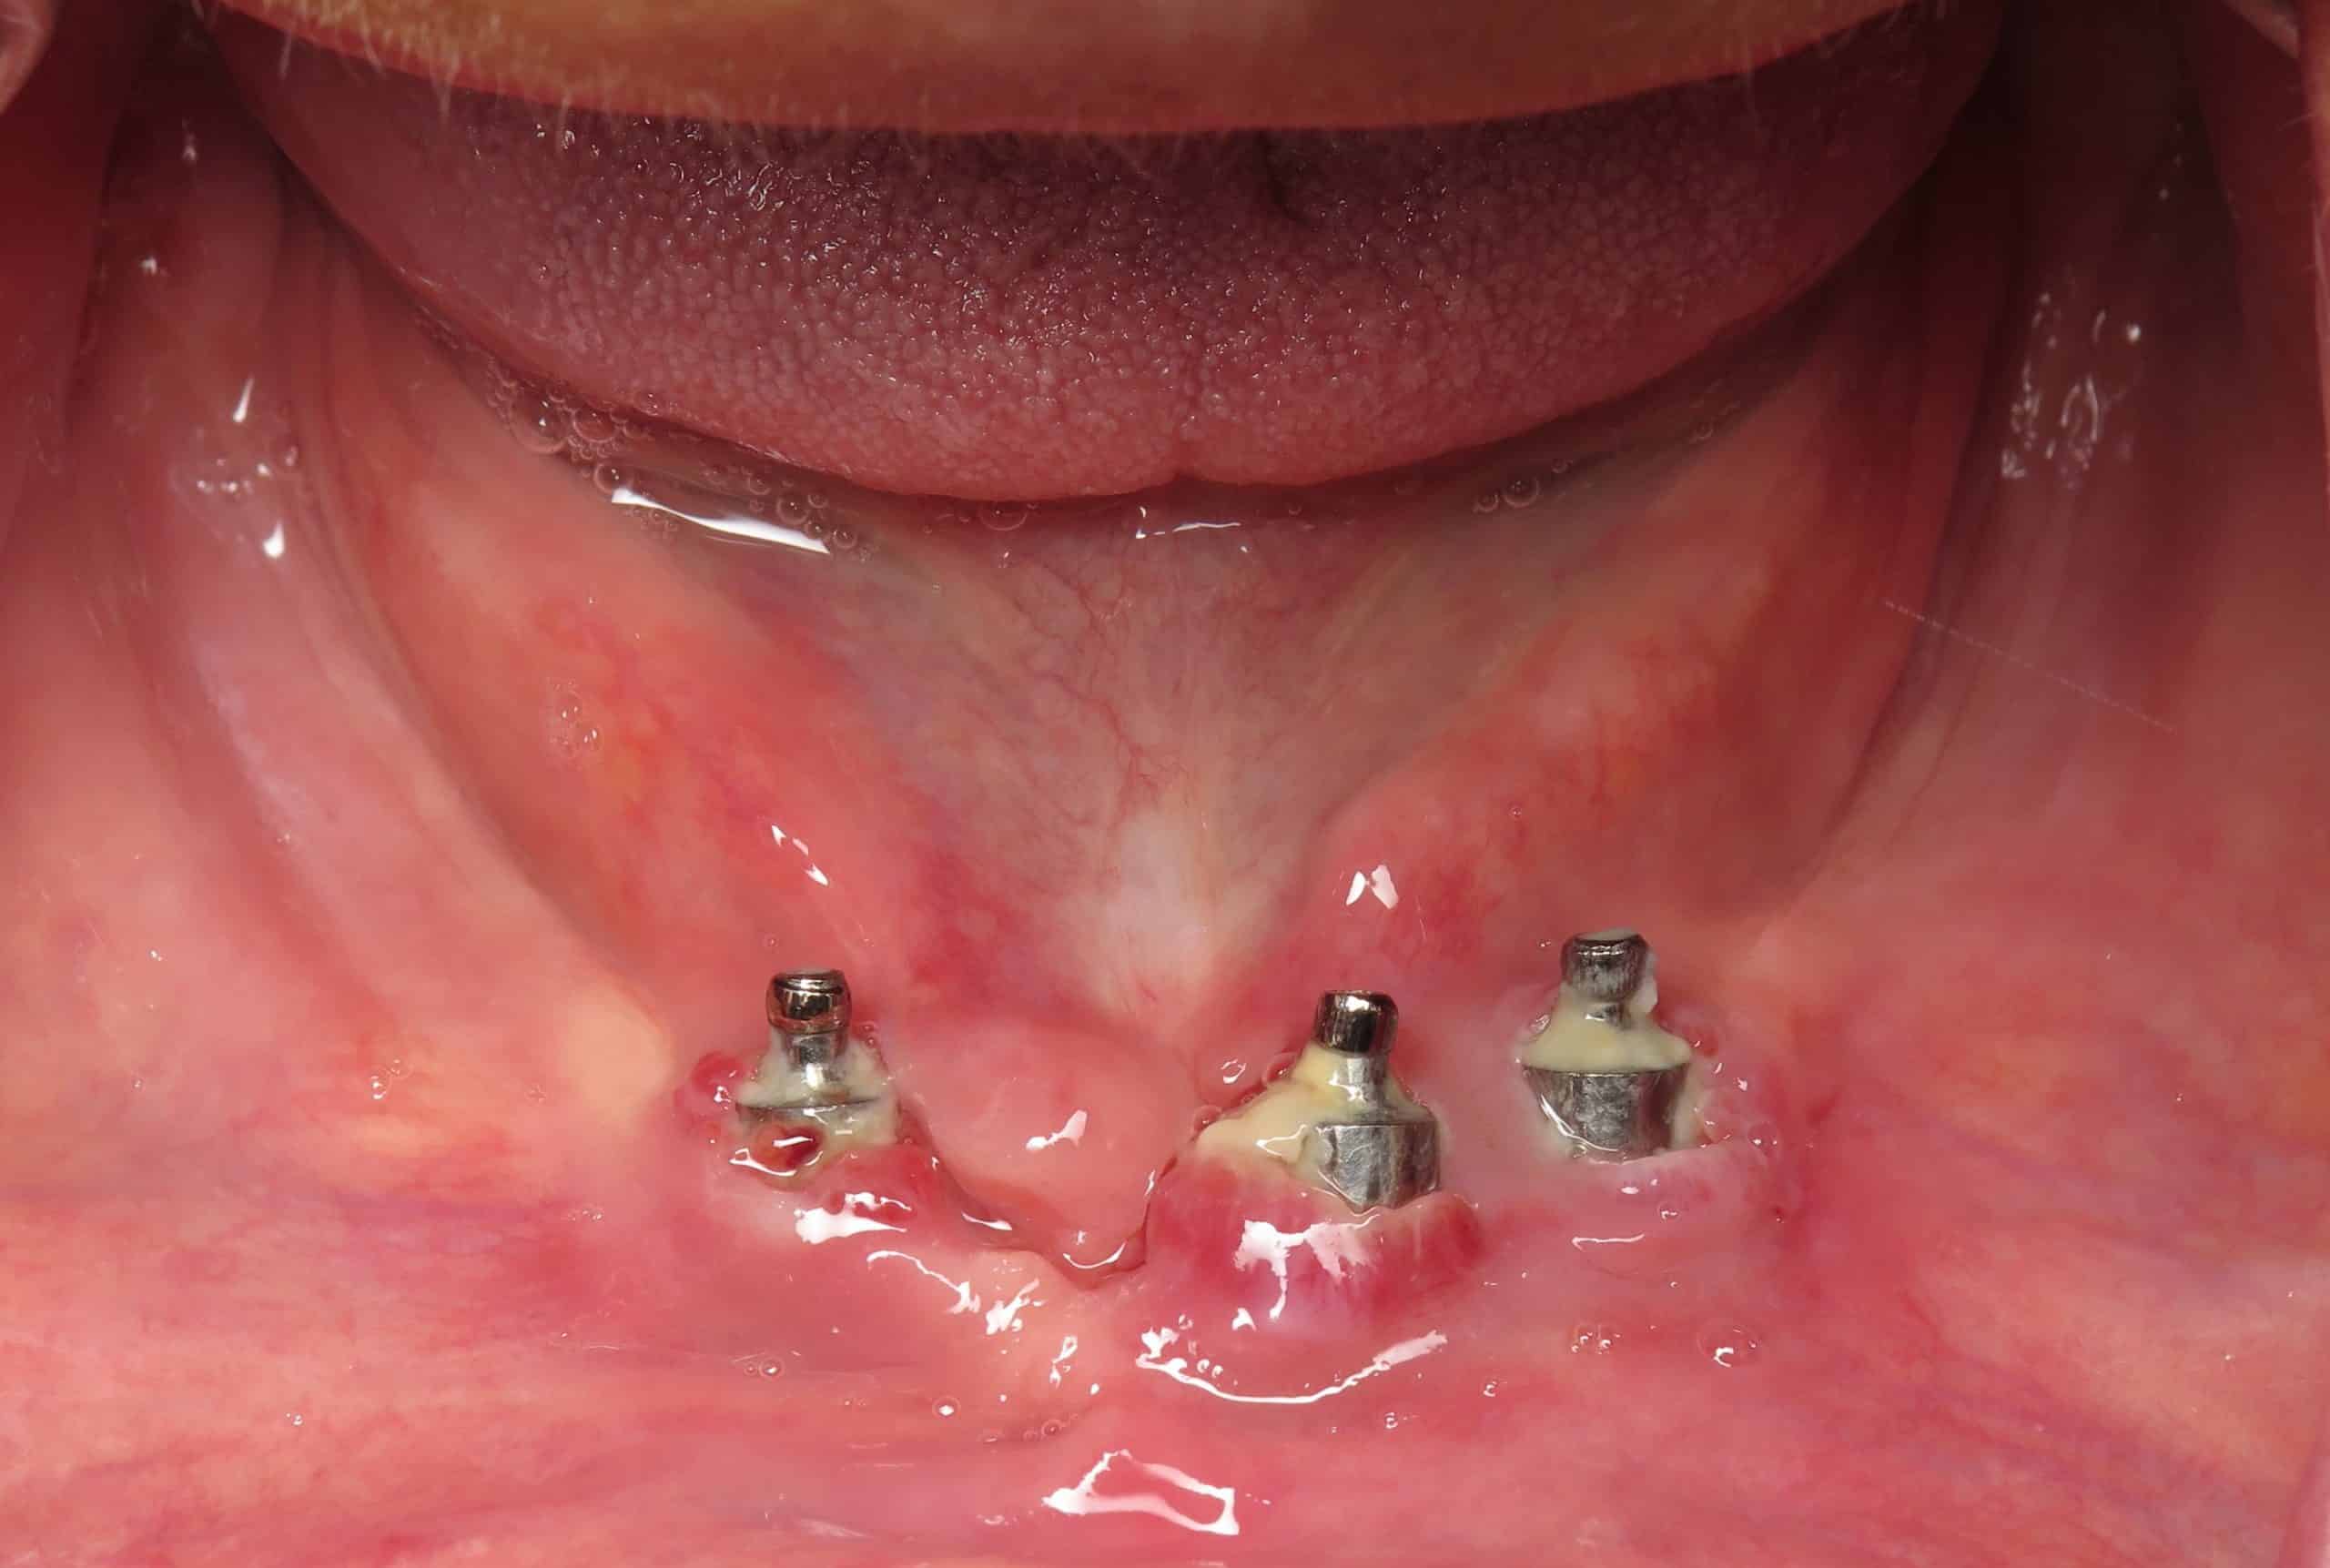

Peri-implantitis develops when plaque builds up around the implant surface. This buildup triggers inflammation in nearby tissues. According to our editor’s research, early signs often include bleeding, swelling, and tenderness. Many patients overlook these symptoms because they mimic mild gum irritation. The condition progresses when bacteria reach deeper layers. These bacteria disrupt the connection between the implant and surrounding bone. As a result, the tissues weaken steadily. Understanding this process guides treatment decisions. Early diagnosis improves outcomes significantly.

Early symptoms help identify peri-implantitis before it progresses. Bleeding during brushing offers an early warning. According to our editor’s research, consistent swelling around the implant also signals trouble. Some patients notice a bad taste or persistent odor. These symptoms reflect bacterial activity. Increased sensitivity while chewing may follow. Color changes in the gums appear in advanced stages. Recognizing these early signs encourages timely treatment. Regular checkups help catch peri-implantitis early. Quick action limits tissue damage.